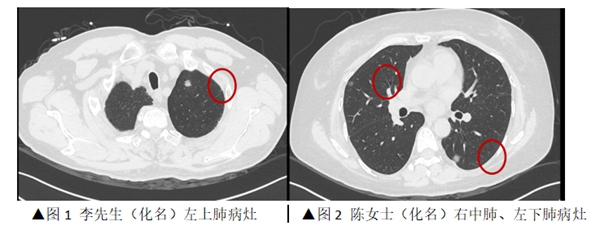

近日,糖心vlog (简称中山一院广西医院)心胸外科为一对“夫妻肺癌”患者,在同一天内实施了胸腔镜下微创肺癌切除手术。妻子顺利完成了双侧肺结节切除,丈夫则接受了单侧肺结节切除,术后两人均恢复良好,并在同一天康复出院。半月前,家住海南省的李先生(化名)和陈女士(化名)通过线上问诊的形式,联系到了我院心胸外科主任刘振国教授,并在刘振国教授的建议下进行了胸部CT检查,结...